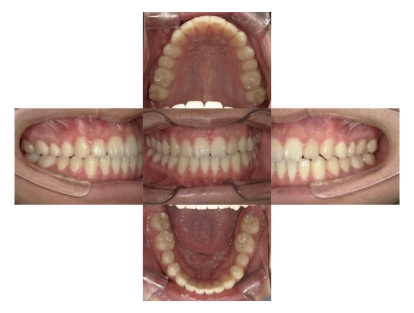

BEFORE

AFTER

症例1

上顎前突、叢生

抜歯

ブラケット矯正

上下顎叢生、上顎前突(出っ歯、上下の前歯のガタガタ)のケースです。

装置はラビアル(上下表側)で、上顎の小臼歯を2本抜歯を行っています。抜歯したスペースを使って、上の前歯の後方移動と叢生(ガタガタ)と出っ歯の改善を行っています。下は歯と歯の間にIPR(隣接面削合)を行い、スペースを確保し、叢生の改善を行っています。

主訴 前歯のガタガタと出っ歯が気になる。

年齢・性別 47歳 女性

お住まいの地域 神奈川県川崎市

治療方針 抜歯スペースおよびIPRを利用して上前歯の叢生(ガタガタ)の改善

抜歯部位 上顎左右第一小臼歯

使用装置 ラビアル(上下表側)、顎間ゴム

治療期間 2年0か月

治療回数 15回

リテーナー クリアリテーナー